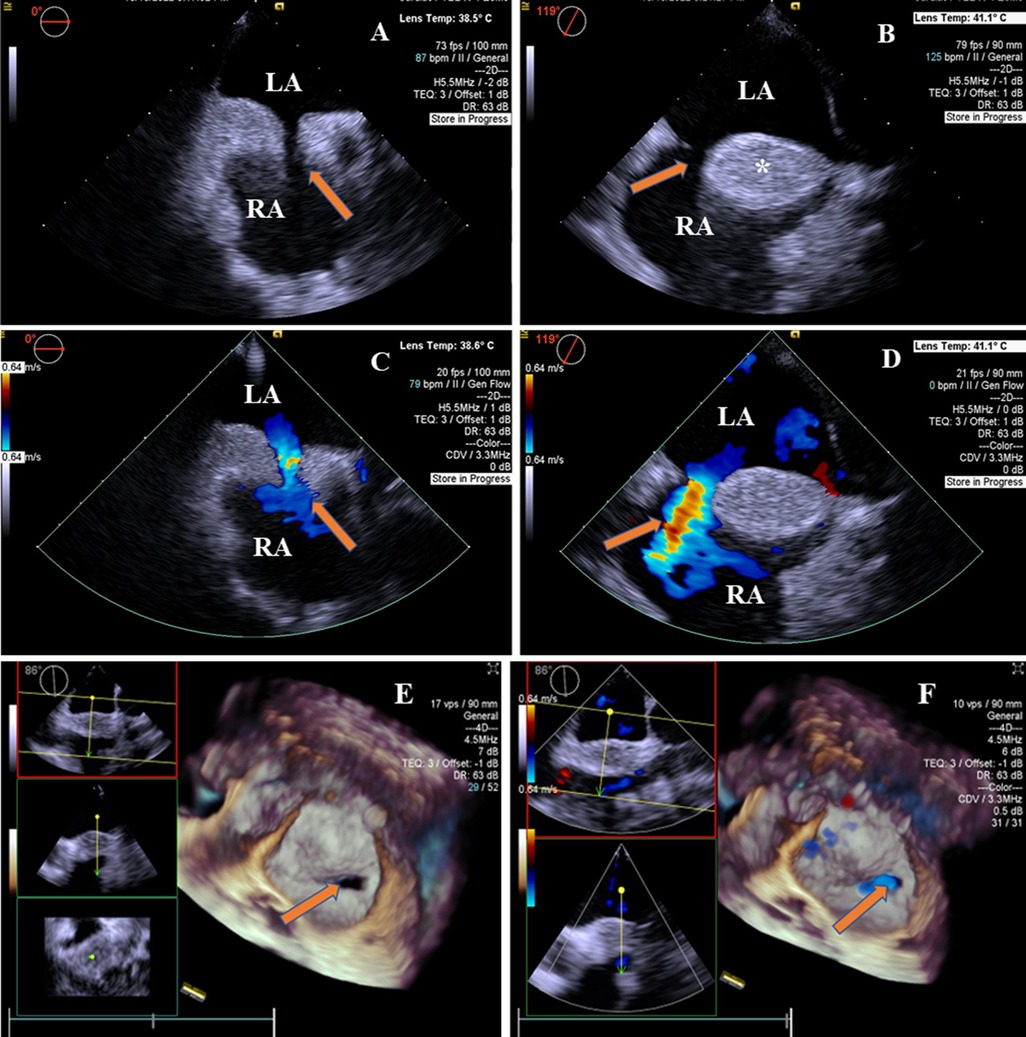

Two-dimensional transesophageal echocardiography revealed a “dumbbell”-shaped involvement of the cephalad and caudal regions with sparing of a single secundum ASD with a size of 9 mm × 13.2 mm. The maximal thickness of the interatrial septum was 20.7 mm, and the thinnest atrial septum was 1.6 mm from the view at 0°–180°. The atrial septum presented with a brightness feature, a rare condition characterized by the deposition of unencapsulated fat cells in this area (Figures 1A,B). There was no obstruction in the superior and inferior vena cava. A two-dimensional color Doppler ultrasound evidenced a left-to-right shunt through ASD (Figures 1C,D). The diagnosis of LASH with ASD was established based on the above findings. Real-time four-dimensional transesophageal echocardiography (RT4D-TEE) confirmed the lipomatous hypertrophy of the atrial septum and an oval-shaped ASD (Figure 1E and Supplementary Movie I). In addition, a color Doppler ultrasound of RT4D-TEE demonstrated the defect appeared foraminal in a location with a significant left-to-right shunt, suggesting a “foraminal” or “fossa” ASD (Figure 1F and Supplementary Movie II).

Figure 1. 2D-TEE and 4D-TEE images revealed lipomatous hypertrophy of the atrial septum with atrial septal defect. (A) On 2D-TEE imaging, a single secundum ASD (arrow) and interatrial septum thickened to 20.7 mm in diameter were observed from 0° view. The septum with brightness features is characterized by the deposition of unencapsulated fat cells in the atrial septum. (B) 2D-TEE further documented a “dumbbell”-shaped involvement of the cephalad and caudal regions with sparing of the fossa ovalis (arrow) from 119° view. The interatrial septal fatty infiltration was demonstrated (*). (C) Color Doppler ultrasound of 2D-TEE showing a blood shunt from the left atrium to the right atrium (arrow) from 0° view. (D) Color Doppler ultrasound of 2D-TEE showing left-to-right shunt through ASD (arrow) from 119° view. (E) RT4D-TEE imaging reflected the whole ASD was surrounded by lipomatous hypertrophy of atrial septum (arrow) from 86° view. (F) Color Doppler ultrasound of RT4D-TEE showing blood flow of the ASD from the left to the right atrium (arrow). LA, left atrium; RA, right atrium.